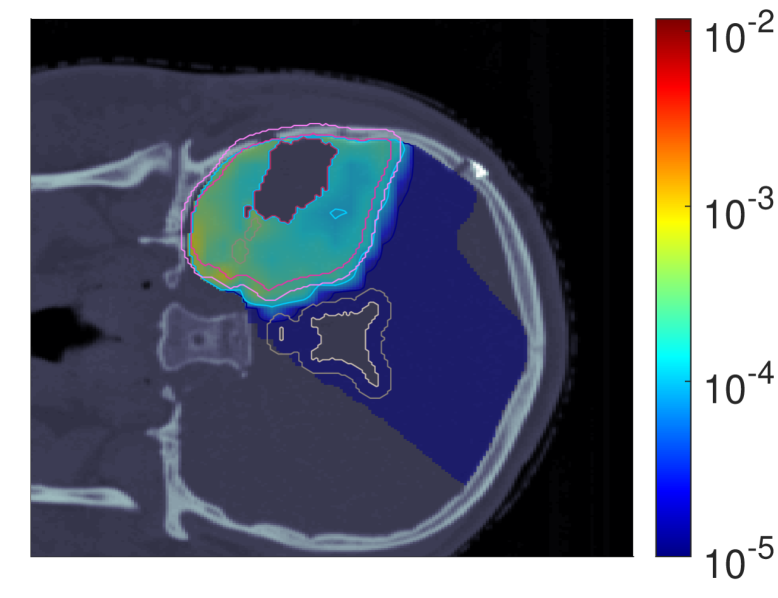

Figure 2 shows the optimal slice images of the dose (left), dose-averaged LET (middle) and POLO distribution (right). On the underlying CT scan, the tumor volumes are marked by violet to purple contours, while the VS (ventricles and 4 mm4\text{\,}\mathrm{mm} fringe) is outlined in white and gray. We observe the high-dose region covering all of the GTV, with a largely homogeneous transition to the clinical and planning target volumes (CTV, PTV), and a moderate to severe overlap to the VS. The dose-averaged LET distributes in layers, with increased values around the contour edge of CTV/PTV and local peaks at the distal ends of the proton beams. Accordingly, hot spots on the POLO map are found in regions where dose and dose-averaged LET scale up, or close to the VS. Beyond the PTV, the POLO map reveals cold spots, due to the steepness of the dose and dose-averaged LET gradients.

dRBE,fxd_{RBE,fx}ABCD ldl_{d}ABCD ppABCD

Refer to caption Refer to caption Refer to caption

NTCP:45.59 %NTCP:$45.59\text{\,}\mathrm{\char 37\relax}$ABCD

Figure 2: Optimal 2D slice images of the RBE-weighted fractional dose dRBE,fxd_{RBE,fx}, the dose-averaged linear energy transfer ldl_{d} and the probability function values pip_{i} for the baseline plan. The dose distribution (left) shows high target coverage with decreasing exposure beyond the CTV/PTV margins, but also visibly overlaps with parts of the VS. Meanwhile, for the dose-averaged LET (middle), layered homogeneity in the target volumes and local maxima at the distal ends of the proton beams can be observed. This results in more pronounced levels of POLO values within the target volumes, particularly in the presence of local dose-averaged LET maxima and in the environment of the VS. Referring back to the POLO model from Equation 1 and (3), we can expect exactly this type of coherence between the model output, the physical input feature profiles and the increased local risk near the VS. The baseline treatment plan exhibits a complication risk of 45.59 %45.59\text{\,}\mathrm{\char 37\relax} after evaluation of the POLO distribution with NTCPpNTCP_{p}.